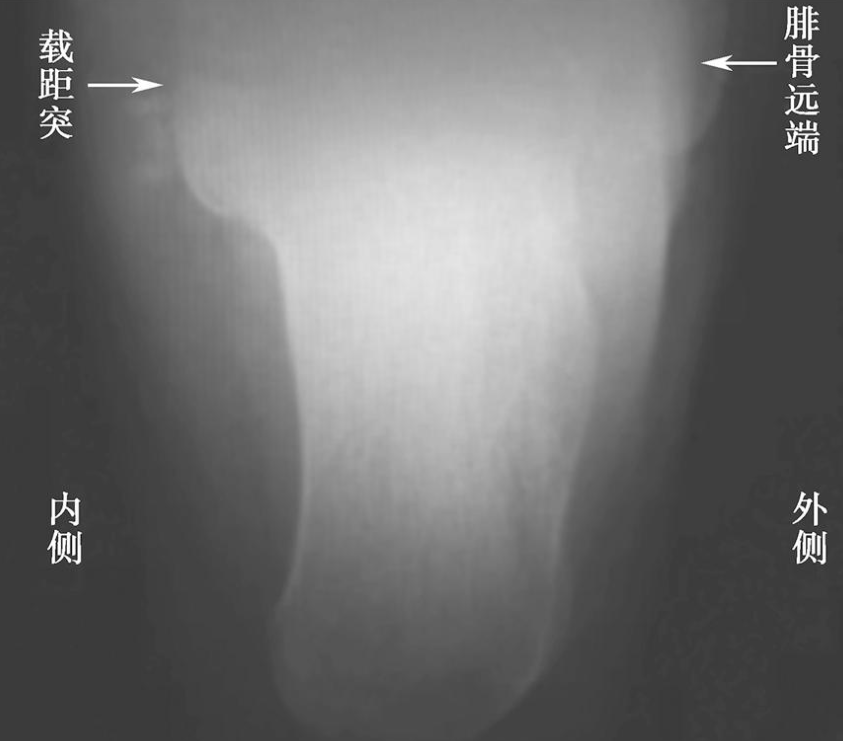

3、轴位X线片:

通常用来确定骨折类型及严重程度。判定预后情况及指导手术方案(图2)。

图2 跟骨轴位像